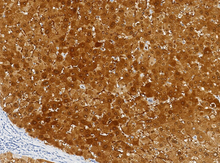

L’arginase-1 est spécifiquement exprimée dans les hépatocytes (tissus bénins et malins). Dans le tissu hépatique normal, l’arginase-1 montre une positivité cytoplasmique diffuse intense dans l’ensemble des lobules, avec une positivité nucléaire focale dans de rares cas. Le carcinome hépatocellulaire présente généralement une expression plus élevée de la protéine ARG1 que les hépatocytes normaux. Cela en fait un marqueur important pour le diagnostic anatomopathologique et le diagnostic différentiel des cancers du foie, en particulier pour distinguer le carcinome hépatocellulaire des tumeurs métastatiques d’origine non hépatique.

Contrôle positif : Tissu hépatique